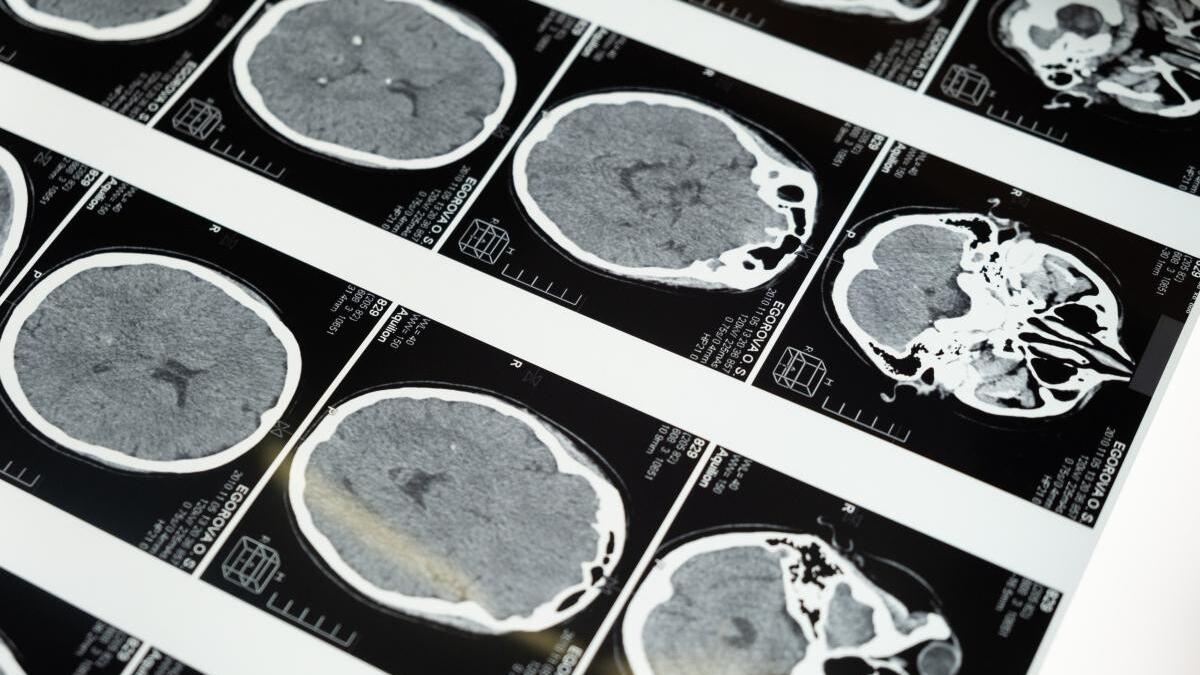

Având un câmp magnetic de 11,7 T (tesla), de zece ori mai puternic decât scanerele RMN din spitalele obișnuite, „Isolda” este rezultatul unei colaborări franco-germane și a peste două decenii de cercetare intensivă. Testele inițiale ale dispozitivului, care au implicat un dovleac ca obiect de studiu, au confirmat că acesta poate furniza imagini incredibil de precise ale structurii cerebrale umane.

Alexandre Vignaud, fizician și director de cercetare la Comisariatul pentru energie atomică și energii regenerabile din Franța (CEA), a subliniat nivelul de precizie fără precedent pe care „Isolda” îl oferă în imagistica cerebrală. El a comparat imaginile obținute cu cele produse de scanerele RMN tradiționale și a evidențiat capacitatea dispozitivului de a afișa detalii minuțioase, cum ar fi vasele mici de sânge care alimentează cortexul cerebral.